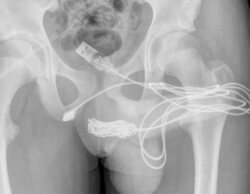

Un joven de 15 años, intervenido de urgencia por introducirse un cable USB para medir el interior de su pene

Su familia se alarmó cuando comenzó a orinar sangre y tuvo que ser transado a urgencia: tendrá un seguimiento por posible estrechamiento de la uretra.